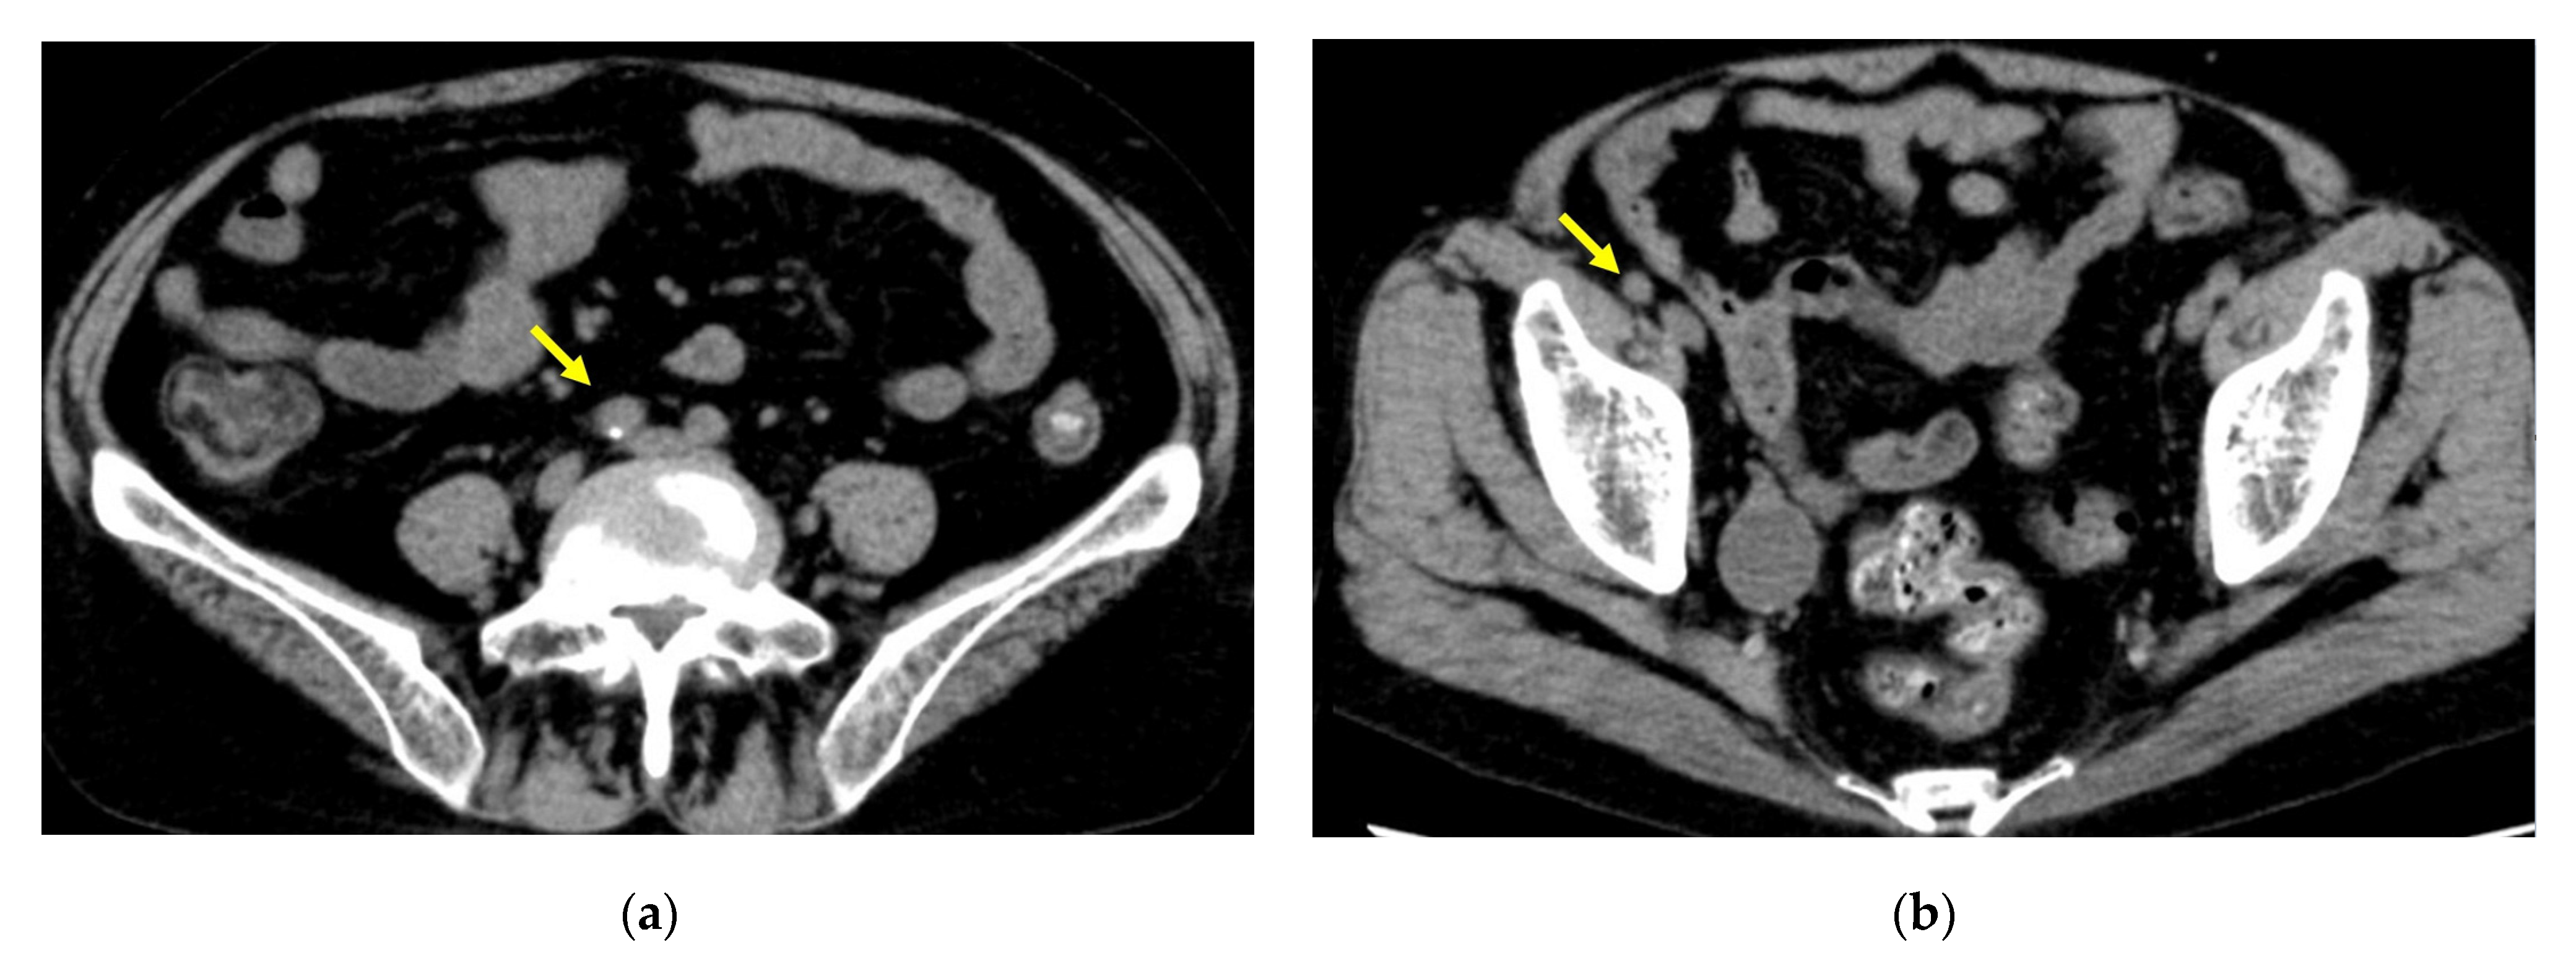

2. Case Report